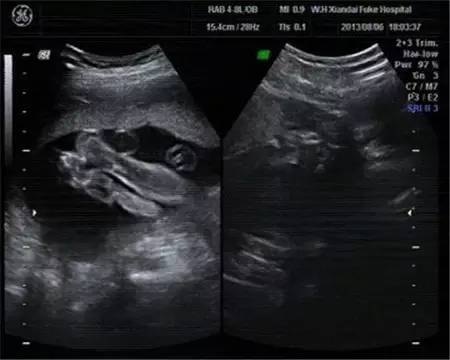

目前世界上最先进的彩色超声设备就是四维彩超。对于孕妇检查来说,这种检查十分准确,而且可以通过各种角度来查看肚子中的宝宝。

我们可以通过四维彩超,清楚的看到宝宝性别。但是我国的法律明令禁止对胎儿性别进行鉴定,所以医生并不会准确告诉你胎儿性别,但是我们可以通过四维彩超的结果来查看宝宝的性别。

从彩超看生男生女?我国严禁查看胎儿性别,医生通过任何途径向孕妇透露或者暗示胎儿的性将会受到法律的追究。所以在做四维彩超时,医生一般会避开胎儿的下半身,不会在图像上显现出胎儿的生殖器官。而且对于年轻的父母来说,无论男宝宝还是女宝宝都是这个家庭的宝贝,了解胎儿的健康发育情况才是做四维彩超的意义。